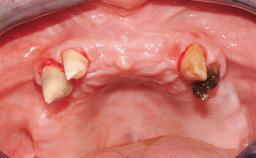

A 63-year-old male patient was referred for a consultation and treatment of partial edentulism in the maxilla. The patient presented with residual anterior teeth and declined a partial removable prosthesis. He reported that the maxillary posterior teeth had been extracted due to mobility and periodontal disease two months before the consultation. The patient’s chief complaint was that his residual maxillary teeth were mobile and that he was unable to chew. The patient’s desire was a stable and comfortable fixed maxillary rehabilitation. The patient was a light smoker (fewer than 10 cigarettes/ day), and his medical history was without significant findings. He was not on any regular medication at the time of consultation. The extraoral examination revealed a normal physiognomy with a correct distribution of the facial thirds. The patient presented a low lip line, and the transition line between teeth and soft tissues was not exposed during a forced smile.

| Infection at Implant Site | None | Chronic | Acute |

| Soft Tissue Anatomy | Intact | Defective | |

| Bone Volume | Horizontally and vertically sufficient | Horizontally deficient | Deficient vertically or deficient vertically AND horizontally |